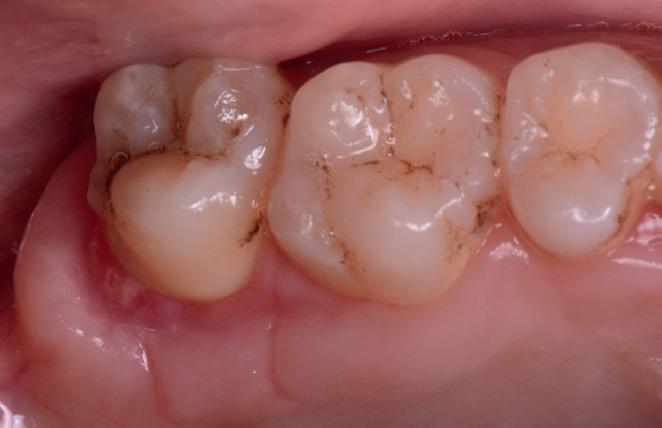

Întotdeauna nuanța este potrivită: Cu proprietățile incredibile de potrivire a nuanțelor, restaurarea devine invizibilă, integrându-se în dentiția înconjurătoare.

Manipularea este eficientă: Cavitățile sunt umplute rapid și ușor, cu straturi până la 4 mm, fără a fi nevoie de un strat de acoperire suplimentar.

Restaurările sunt de lungă durată: Stresul scăzut de contracție și rezistența ridicată la fracturare și uzură asigură restaurări durabile care rezistă la forța de masticație puternică din zona posterioară.